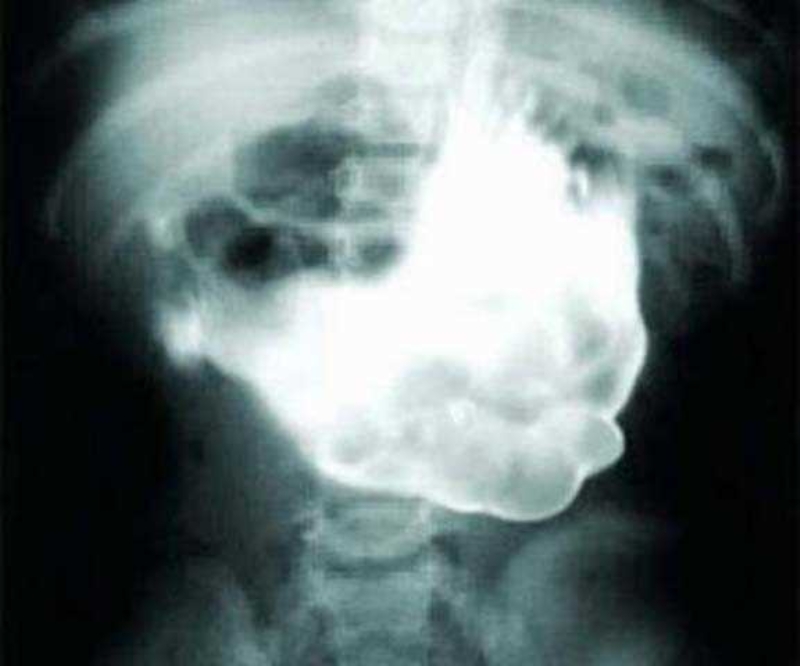

проглотил стекло

Что будет если случайно проглотил стекло 107 фотографий